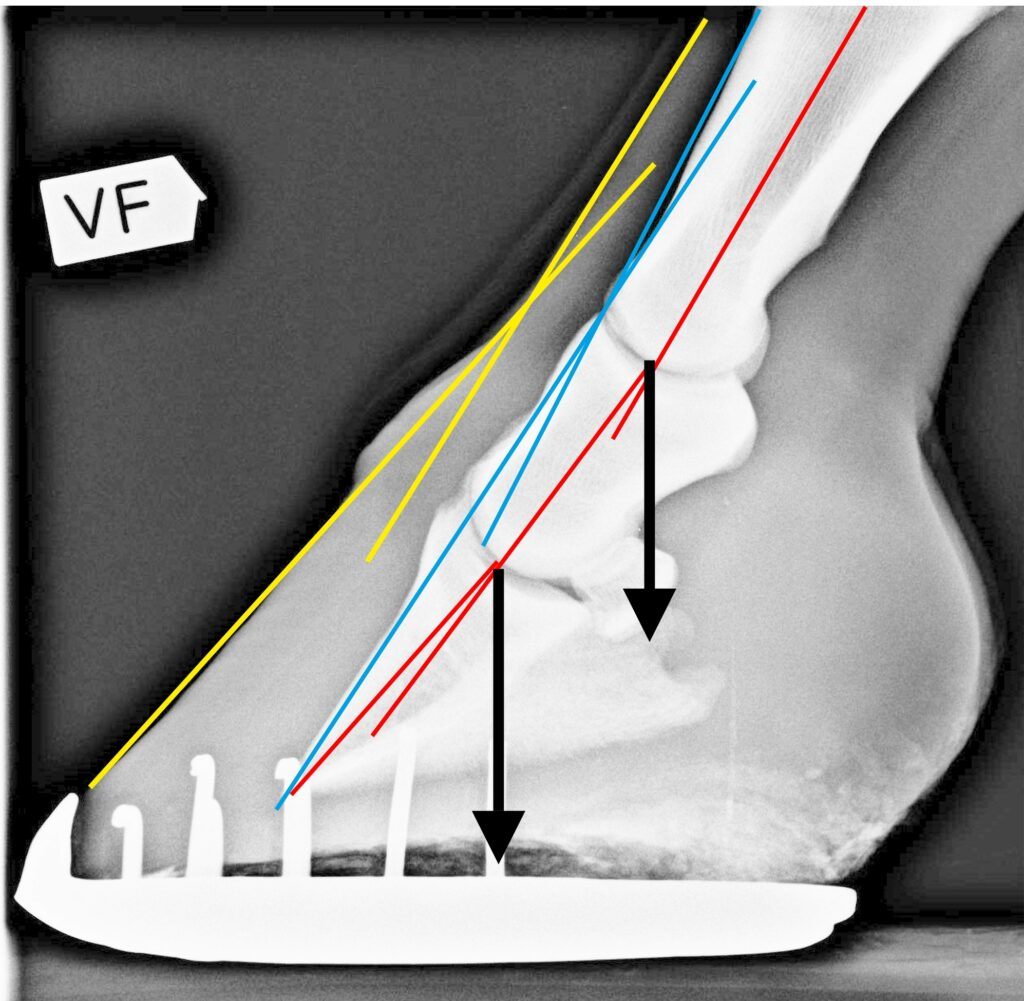

Toe axis, broken or not, is a purely theoretical concept. They say that the lowest three phalanges (P1, P2, P3) in the horse’s leg are supposed to be aligned (as the red line in the picture below) or the horse is suffering from a broken toe axis. There are multiple problems with this reasoning. As you can see in the picture above, there is no standard or fixed angle on the lower three phalanges when the horse is moving. It is alldepending on the loading of the hoof. Yes, I’ve heard that you are supposed to check the toe axis when the horse is standing still, in balance, on a flat surface. But why, when standing still on a flat surface, are stresses and strains the smallest? Even if you have your horse standing still on a flat surface, the toe axis will change as soon as he looks to the side. And how do you check the angles of the skeletal bones when the only thing you can see is fur, and a hoof capsule that is only loosely connected to the coffin bone (yellow line). These are, however, just details because the main argument against the toe axis is that there is no force going in the direction of the theoretical toe axis, ever, which makes the complete reasoning about the toe axis completely irrelevant.

The yellow lines are what you can see: fur and hoof capsule.

The blue lines are the outside of the skeletal bones (which would be closest to what you can see from the outside), but they are not parallel to the yellow lines, and you can’t see them from the outside.

The red lines, which are the only things that could have any relevance, are still just lines since there is no forces going in that direction.

The force created by the horse’s weight and gravity that is pushing the hooves to the ground is always aimed straight down, regardless of the angles of the hoof capsule, the fur, and the skeletal bones. The skeletal bones are to be considered building blocks kept together by ligaments and muscles, but the force transferring the weight from the bulk of the horse to the ground is always angled straight towards the centre of the Earth (black arrows).